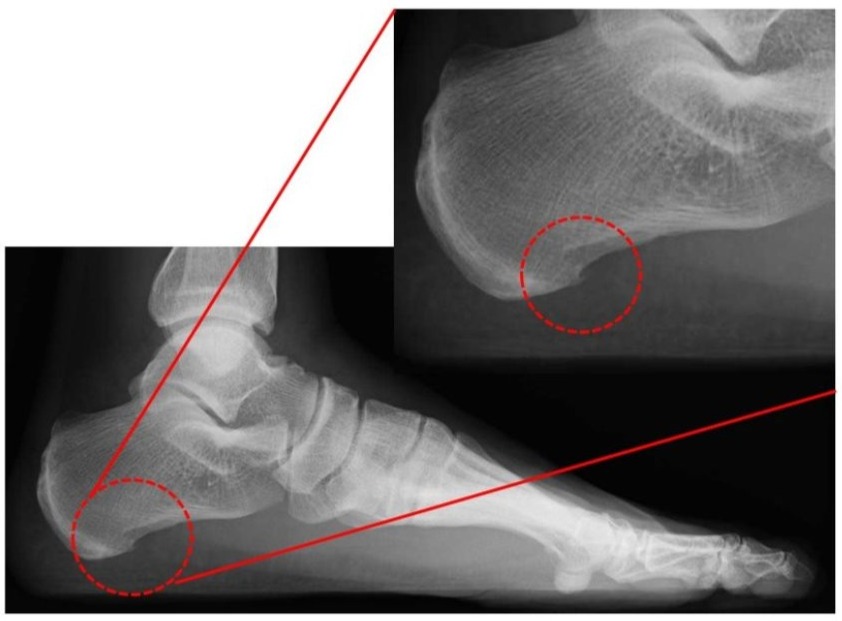

足の裏には、「足底腱膜(そくていけんまく)」という、かかとの骨から足の指の付け根まで伸びる膜状の組織があります。足底腱膜は足のアーチ(土踏まず)を支えて、衝撃を吸収して、足を安定させる役割があります。足底腱膜炎とは、足底腱膜のかかと側の付着部で炎症が起きて、痛みを生じた状態をいいます。主に荷重時の痛みであり、起床時の最初の1歩が最も痛いと訴えられる患者様が多いのも特徴です。足底腱膜炎は40~60代の方、高体重、ランニングなどで足に負担がかかりやすい方、扁平足傾向(足の土踏まずが潰れてしまっている状態)、足関節の柔軟性低下などが発症のリスク因子とされています1)2)3)。患部へ負担がかかり続けると、足底腱膜が分厚く変性(肥厚)、骨のトゲ(骨棘)の発生、腱内部の異常血管の侵入や痛みを知覚するための神経線維の過剰な増加などの変化が起こり、痛みの改善までに時間がかかる場合があります。(図1,2)。

図1 踵の骨(踵骨)に骨のトゲ(骨棘)が見られるレントゲン画像